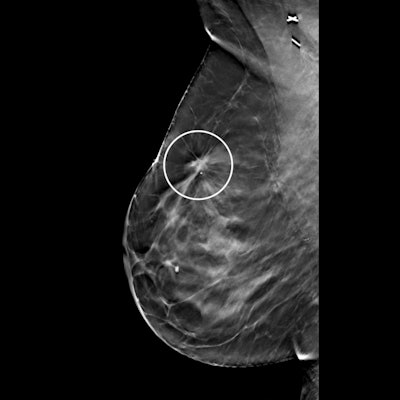

The benefits of digital breast tomosynthesis (DBT) may be limited for finding additional cancers in breast cancer survivors, according to a December 22 study in Radiology. While DBT led to fewer recalls, the modality didn't boost the cancer detection rate for this high-risk population.

"Among breast cancer survivors, screening with digital breast tomosynthesis led to fewer false-positive results and higher specificity but did not affect cancer detection," wrote the authors, led by Dr. Manisha Bahl, director of the breast imaging fellowship program at Massachusetts General Hospital.

Bahl and colleagues found that DBT led to a lower abnormal image interpretation rate and higher specificity than digital mammography in this population. But the overall and invasive cancer detection rates did not differ between the two modalities.

The findings led the authors to question the clinical relevance of DBT for women with a personal history of breast cancer. Although significant, the absolute reduction in the abnormal image interpretation rate was fairly small at 0.4%. Still, the higher specificity could be a benefit for women with prior cancer by reducing the number of women recommended for biopsy.